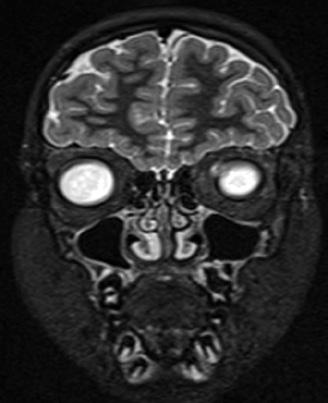

Evaluare RMN - absența congenitală a bulbului olfactiv

Clinica ORL a Spitalului Clinic „Sfânta Maria” din București a beneficiat de primul centru din România pentru evaluarea funcției olfactive prin metode subiective (olfactometrie dinamică ce utilizează n-Butanol, Snap and Sniff Test) și obiective (potențiale evocate electrice olfactive) deschis în 2016. Experiența evaluării olfactive a crescut de la an la an mai ales în contextul sensibilizării pacienților de tulburările olfactive din pandemia Covid 19. Sunt săptămânal evaluați pacienți cu tulburări olfactive secundare infecțiilor și inflamațiilor rinosinuzale dar și cu anosmii posttraumatice în context medicolegal. Un grup important de pacienți sunt cei care acuză

Investigații imagistice

Deși în literatura de specialitate sunt subliniate utilitatea și importanța investigațiilor imagistice (computer tomograf cerebral și sinusuri, dar mai ales RMN cerebral cu identificarea și măsurarea bulbului olfactiv), conform experienței noastre, mare parte din pacienți nu sunt investigați imagistic. Principalul motiv este cel financiar, deoarece examinările imagistice au costuri ridicate pe care cei mai mulți dintre pacienți nu și le permit, și pe care asigurările medicale nu le decontează [33, 34, 35] .